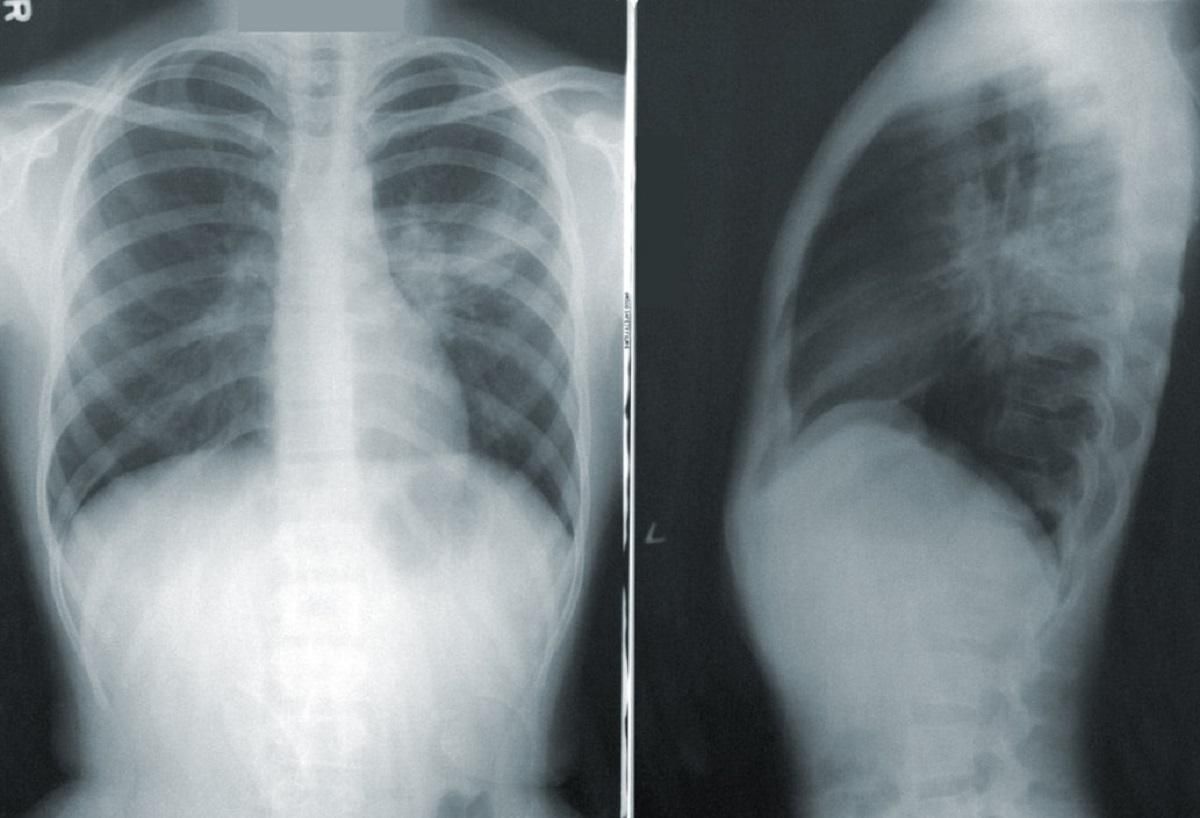

Сегодня мы тестируем все пневмонии, которые находятся в инфекционных больницах, а также больницах другого профиля,

Отметим, что некоторые регионы начали и раньше тестировать всех пациентов с диагнозом пневмония, в частности Киев.